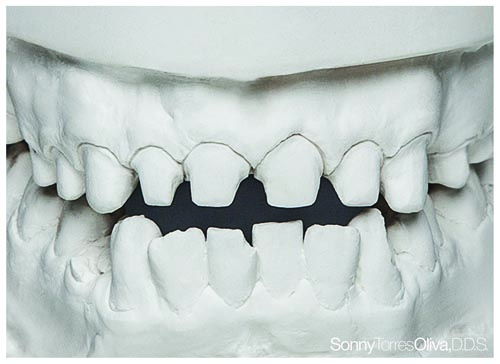

Fig. 11: Preoperative models were mounted, studied and used to determine ratios that should be incorporated into the restoration designs.